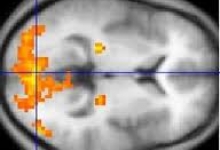

Neuroimagistica

Numarul de modalitati utilizate de neuroimagistica a crescut simtitor in ultimii zece ani. Selectarea corespunzatoare si interpretarea acestor teste este o parte separata in practica neurooftalmologica. Toate mijloacele posibile au anumite avantaje si dezavantaje si este de datoria medicului sa ceara aceste teste fiind sigur ca testul solicitat este cel potrivit. Inainte de a se decide asupra unei